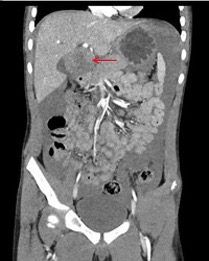

Diagnostic testing. Bedside testing showed a point-of-care hemoglobin level of 10.1 g/dL and a positive Focused Assessment with Sonography for Trauma (FAST) test, with concern for fluid seen in Morison pouch/hepatorenal recess. Other laboratory test results showed a normal complete blood cell count, normal electrolyte level, normal liver enzyme level, and normal lipase levels. Because the patient was hemodynamically stable, a computed tomography (CT) scan of the abdomen and pelvis was obtained (Figures 1a and 1b), showing a large-volume hemoperitoneum with a round, actively-bleeding mass measuring 5 × 5.3 cm in the left hepatic lobe. The CT scan was interpreted by the radiologist as developing hematoma vs a primary hepatic mass with subsequent hemorrhage.

Figure. Coronal (a, top) and axial (b, bottom) views of the CT abdomen/pelvis showing a large volume hemoperitoneum with a round, actively-bleeding mass measuring 5 × 5.3 cm in segment IVb of the left hepatic lobe (red arrows).